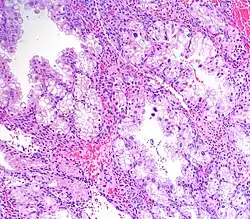

Arias-Stella reaction, also Arias-Stella phenomenon, is a benign change in the endometrium associated with the presence of chorionic tissue.[1]

Arias-Stella reaction is due to progesterone primarily. Cytologically, it resembles a malignancy and, historically, it was misdiagnosed as endometrial cancer.[1]

It is characterized by nuclear enlargement and may also have any of the following: an irregular nuclear membrane, granular chromatin, centronuclear vacuolization, and pseudonuclear inclusions.[1]

Five subtypes are recognized:[1]

- Minimal atypia.

- Early secretory pattern.

- Secretory or hypersecretory pattern.

- Regenerative, proliferative or nonsecretory pattern.

- Monstrous cell pattern.